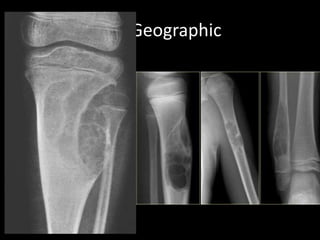

Geographic Bone Destruction

• Destructive lesion with sharply defined border

• Implies a less-aggressive, more slow-growing, benign

process

• Narrow transition zone

e.g

– Non-ossifying fibroma

– Chondromyxoid fibroma

– Eosinophilic granuloma

Geographic